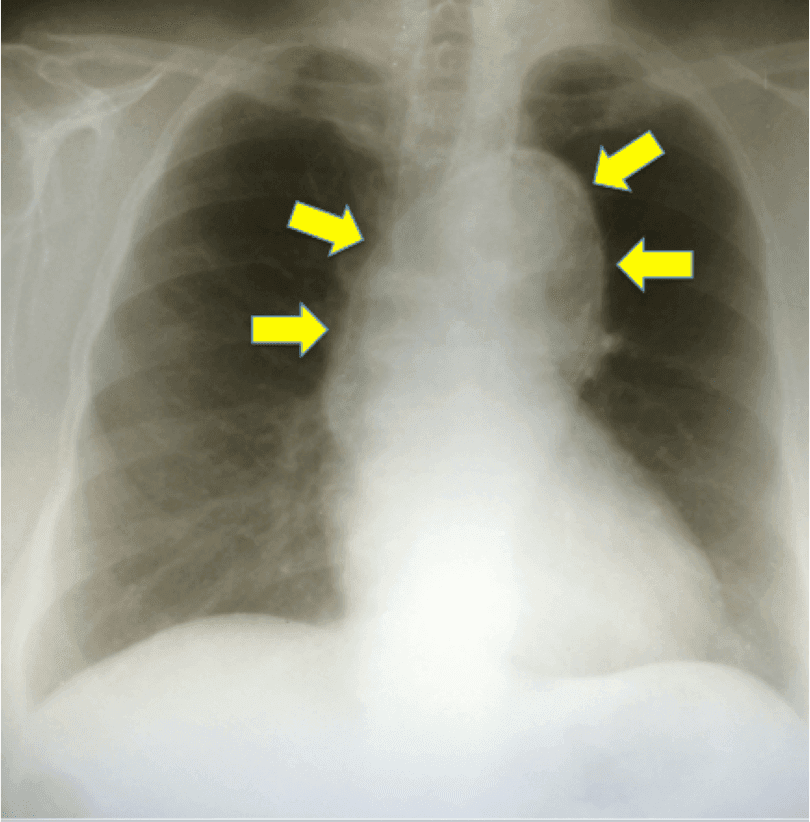

Paciente masculino, 72 años, con queja de dolor abdominal continuo enmesogástrio hace 3 días refractaria a analgésicos convencionales. En el examen físico, se encuentra normal hemodinámicamente y pres…

Paciente masculino, 72 anos, com queixa de dor abdominal contínua em mesogástrio há 3 dias refratária a analgésicos convencionais. No exame físico, encontra-se normal hemodinamicamente e presença de m…